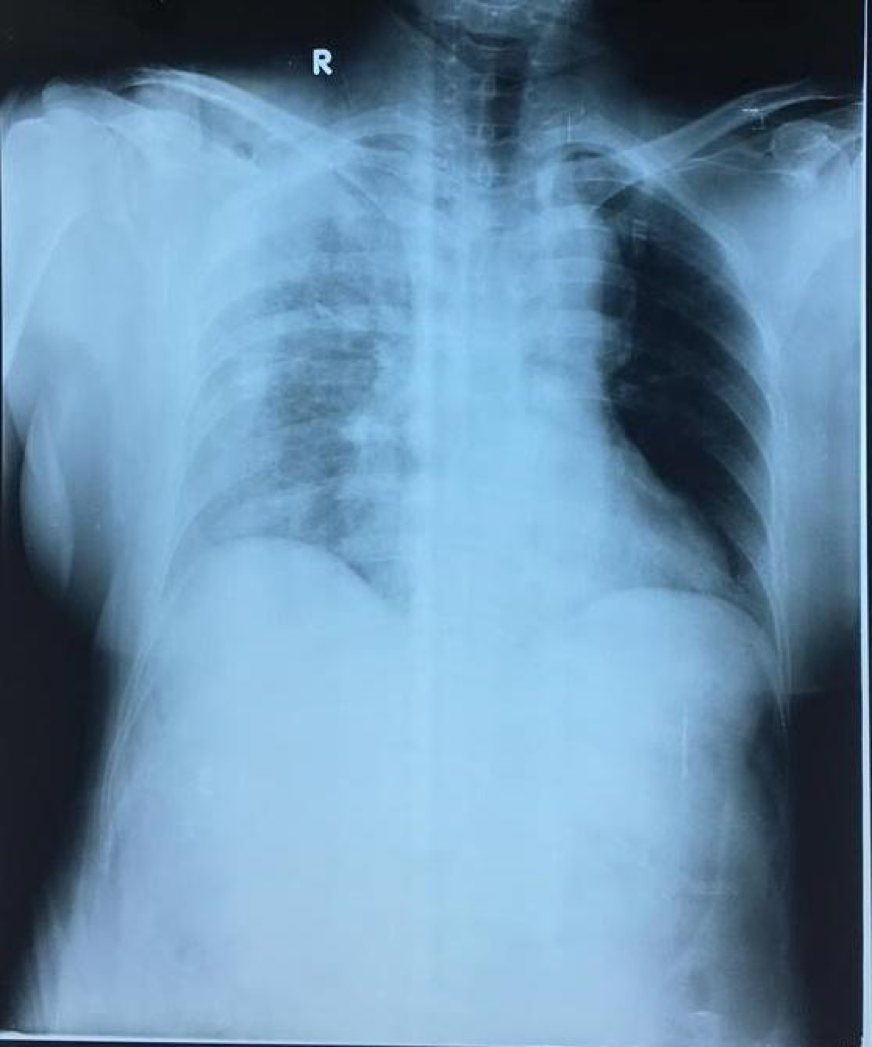

13giờ 47phút ngày 26/4, khoa Cấp cứu bệnh viện Đức Giang tiếp nhận một bệnh nhân được người nhà đưa vào với tình trạng shock nặng đa chấn thương: mạch nhanh nhỏ, huyết áp 80/50 mmHg, khó thở, nhịp thở trên 25lần/phút, sPO2 85%.

Ngay lập tức bệnh nhân được các bác sĩ tiến hành cấp cứu: Thở oxy mask, đặt 3 đường truyền tĩnh mạch, giảm đau, băng cầm máu các vết thương. Qua thăm khám lâm sàng và các xét nghiệm cận lâm sàng tại giường (chụp XQ ngực, siêu âm tổng quát, huyết học).

Bệnh nhân được chẩn đoán: Đa chấn thương, shock mất máu/suy hô hấp tràn máu tràn khí màng phổi bên phải do vết thương thấu ngực/nhóm máu O Rh(-). Lãnh đạo bệnh viện tổ chức hội chẩn các chuyên khoa tại chỗ, xác định tình trạng bệnh nhân rất nặng, nhóm máu hiếm, tuy nhiên phải can thiệp mổ cấp cứu ngay mới có thể giữ được tính mạng người bệnh.

Bệnh nhân được đưa lên bàn mổ lúc 15h. Tiến hành dẫn lưu màng phổi tối thiểu hút ra 500ml máu khí. Tiếp tục đặt ống nội khí quản gây mê toàn thân, vừa đánh giá vừa xử trí các vết thương cụ thể: Vết thương thấu ngực do dao đâm từ bả vai (P) xuyên từ sau ra trước gây tổn thương rách da 10 cm, gãy xương vai, đứt lìa ba xương sườn 4,5,6 gây tràn máu, tràn khí màng phổi (P).